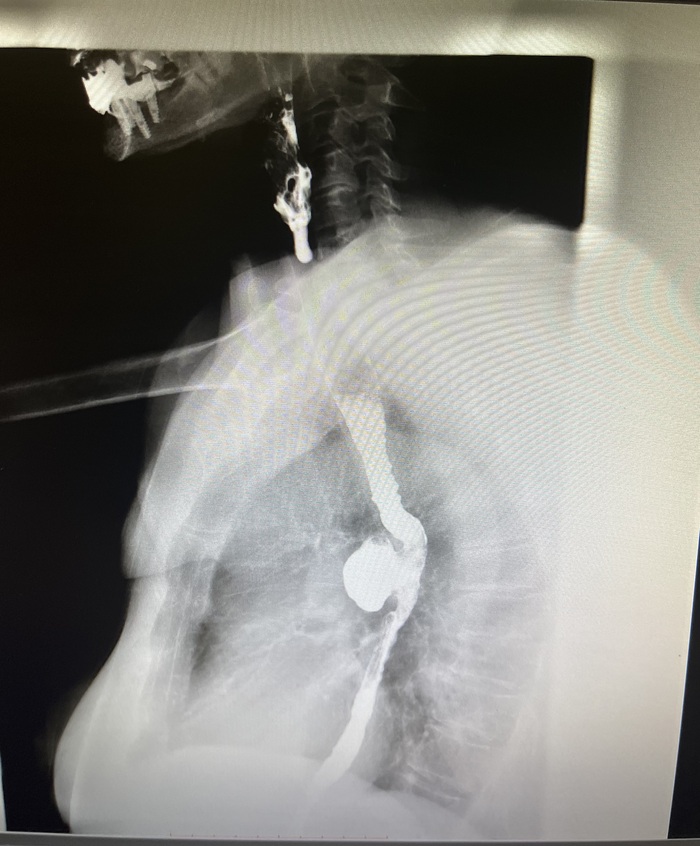

2 снимка маммографии.

На обоих рак молочной железы, но какая разная ситуация.

На 2 снимке опухоль распространена в молочной железе и регионарных л/узлах (в данном случае - это 3 стадия). Организм кричит о беде. Опухоль видна визуально, отмечается уплотнение, изменение формы молочной железы, пальпируются л/узлы. Опухоль может прорастать в кожу, вызывая её изменение (симптом «лимонной корочки», покраснение, язва), или в мышцу. Но главный признак — поражение регионарных лимфоузлов в подмышечной впадине, около ключицы или грудины. Могут появиться боли, дискомфорт, отёк руки. Организм уже тратит силы на борьбу, поэтому возможны усталость и недомогание.